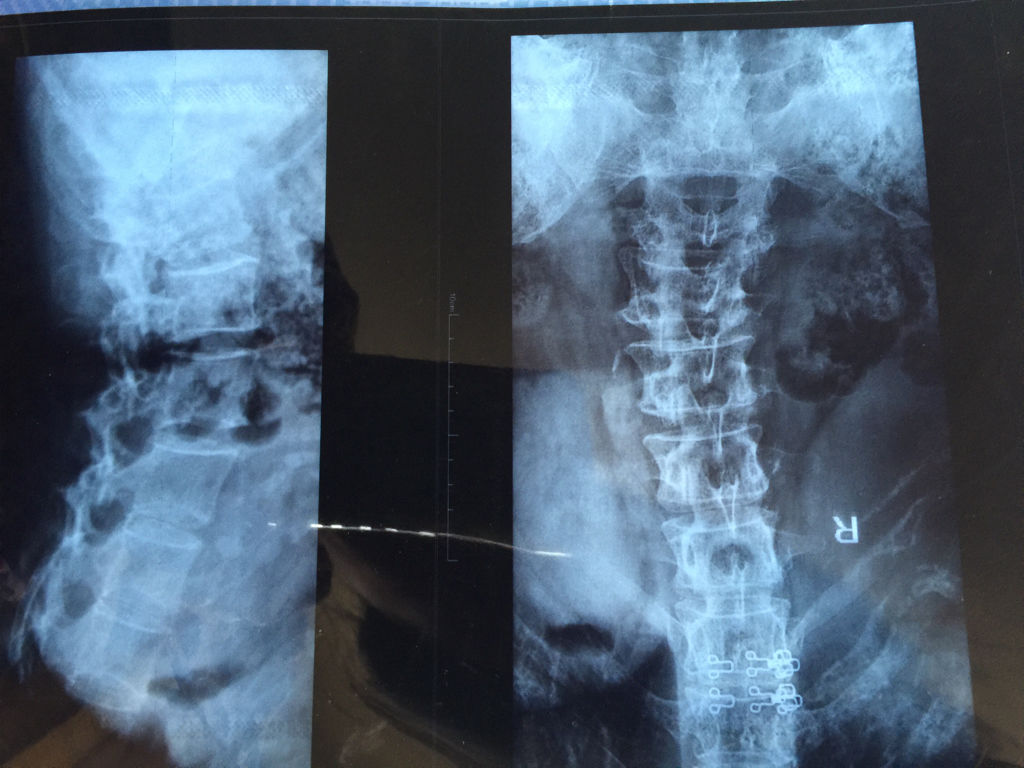

可能扭伤了,去医院拍个片子吧  追问 前天拍的片子,医生说是腰椎侧弯